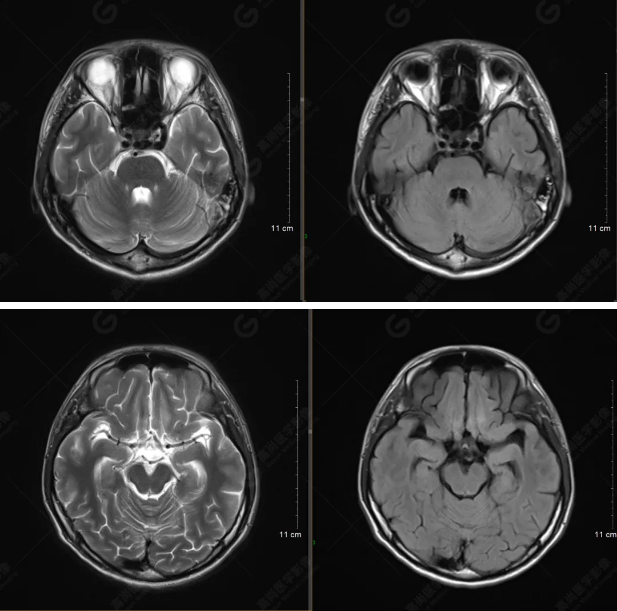

以下是平掃T2WI及FLAIR序列:

雙側(cè)大腦半球?qū)ΨQ,灰白質(zhì)對比正常,顱內(nèi)未見異常信號影。腦室系統(tǒng)未見擴(kuò)大,中線結(jié)構(gòu)居中。腦溝、裂未見增寬。幕下小腦、腦干未見異常。矢狀位示垂體形態(tài)、大小級信號未見異常。所示左側(cè)乳突內(nèi)見多發(fā)短T1長T2信號影。

顱腦MRI平掃未見明顯異常,左側(cè)乳突內(nèi)積血,建議補充SWI檢查。